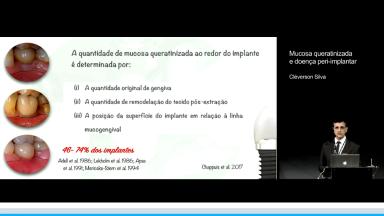

Mucosa queratinizada e doença peri-implantar

Nesta apresentação são demosntrados os conceitos quanto a importância de mucosa ceratinizada ao redor de implantes e sua relação com saúde ou doença periimplantar. Resultados de pesquisas nesse campo mostram que a presença de mucosa ceratinizada tende a diminuir o acúmulo de placa e o desenvolvimento de doenças periimplantares, tais como mucosite e periimplantite. Quando se tem pouca quantidade ou ausência, sugere-se a necessidade de procedimentos para aumentar ou criar mucosa ceratinizada para uma melhor estabilidade tecidual ao longo dos anos.

- explicar a importância de mucosa ceratinizada para saúde periimplantar

- identificar os fatores de risco relacionados a ausência de mucosa ceratinizada

- discutir a importância de procedimentos cirúrgicos para criar ou aumentar mucosa ceratinizada